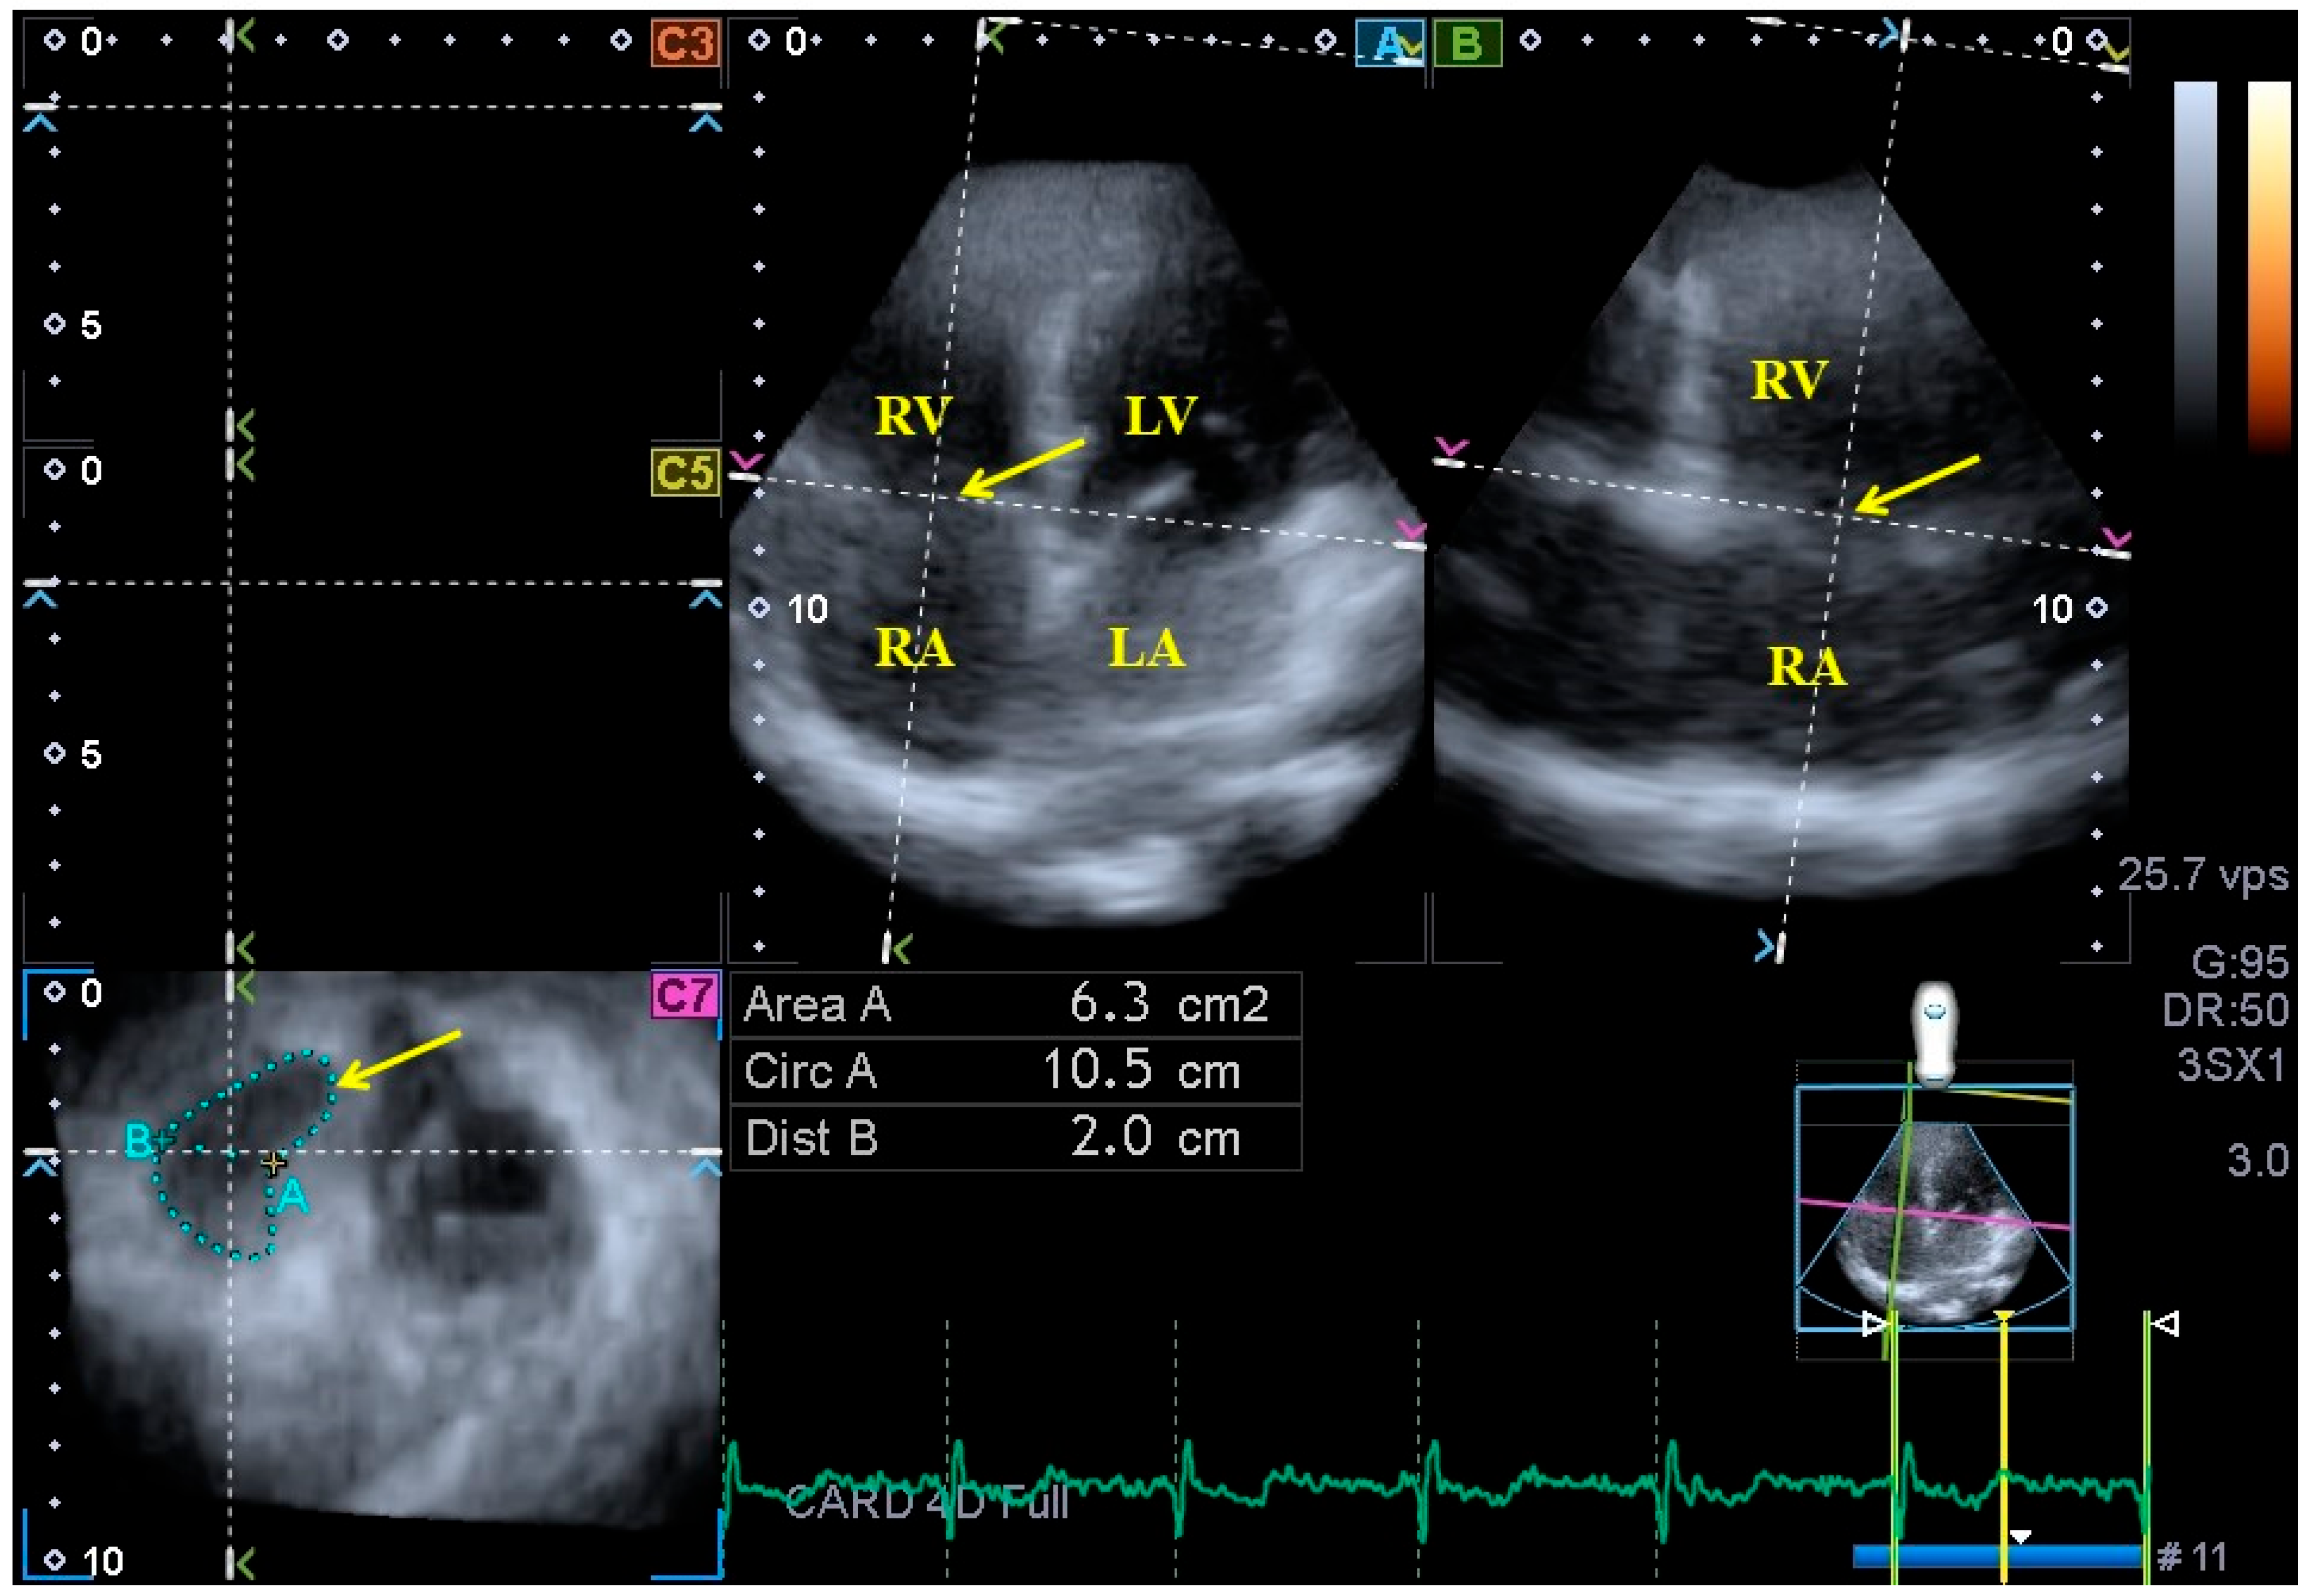

Three-dimensional echocardiography. The aforementioned Toshiba ArtidaTM cardiac ultrasound equipment attached to a PST-25SX matrix array transducer was used for 3DE examinations [5,6,7]. In accordance with our routines, pyramid-shaped 3D echocardiographic datasets were acquired from the apical window. Data were collected during six constant RR intervals seen on the ECG and during one breath hold, and an offline analysis was performed with the vendor-provided 3D Wall Motion-Tracking software (Ultra Extend, Toshiba Medical Systems, Tokyo, Japan, version 2.7) at a later date. Using the abovementioned 3D datasets, the software automatically selected apical two- (AP2CH) and four-chamber (AP4CH) views and 3 short-axis views at basal, midventricular and apical LV levels at end-diastole. Following the definition of the lateral and septal edges of the LV - mitral annulus and endocardial surface of the apical LV, a sequential analysis was conducted in order to create a 3D echocardiographic LV cast. Moreover, AP2CH and AP4CH views were helped to find the optimal TA level on the C7 short-axis view. Directly before tricuspid valve closure at end-diastole and directly before tricuspid valve opening at end-systole, the following TA morphological and functional parameters were calculated (Figure 2) [8,11,19].

Figure 2. Assessment of the tricuspid annulus extracted from a three-dimensional full-volume dataset is presented: apical four-chamber view (A); apical two-chamber view (B); and a cross-sectional view at the level of the tricuspid annulus optimized in apical four- and two-chamber views (C7). The yellow arrow represents the tricuspid annular plane. Abbreviations: LA = left atrium, LV = left ventricle, RA = right atrium, RV = right ventricle, Area = TA area, Circ = TA perimeter, Dist = TA diameter.